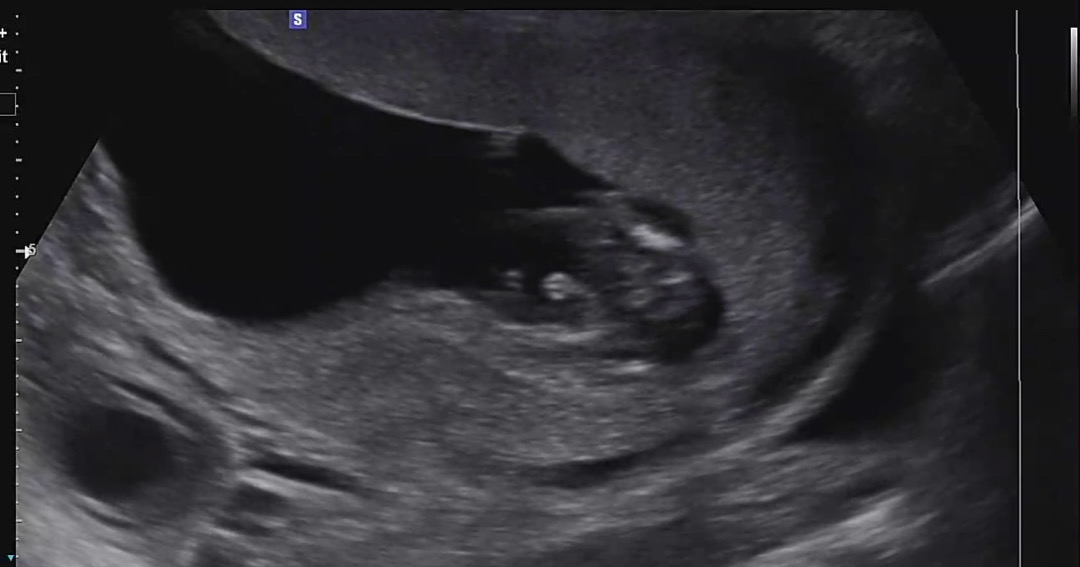

13주 5일 사진 아들 확정일까요?? 😆

가운데 아들 확정일까요?? 혹시 탯줄이 찍혓거나.. 주수가 13주5일이면 이른 건가 싶어서.. 16주나 20주에 반전이 있을까요? (아들도 좋습니당ㅋㅋ 다만 어른들께 말하려고 해서 궁금하네요!)